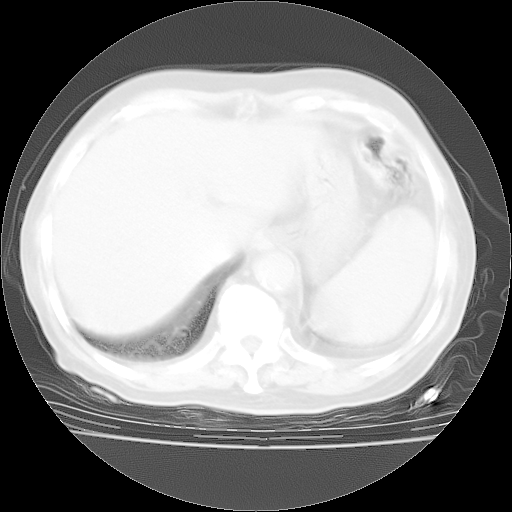

今天部分检查

轻微咳嗽,无痰,(体温正常时)R20次/分,P75次/分,双肺底、腋下可闻及少量捻发音。下肢轻度浮肿。

腹部B超:胆囊壁增厚,肝、胆、胰、脾、肾无异常,肠系膜淋巴结、腹膜后淋巴结无增大。

ECG:右心室增大

心脏超声检查:无右心室增大。